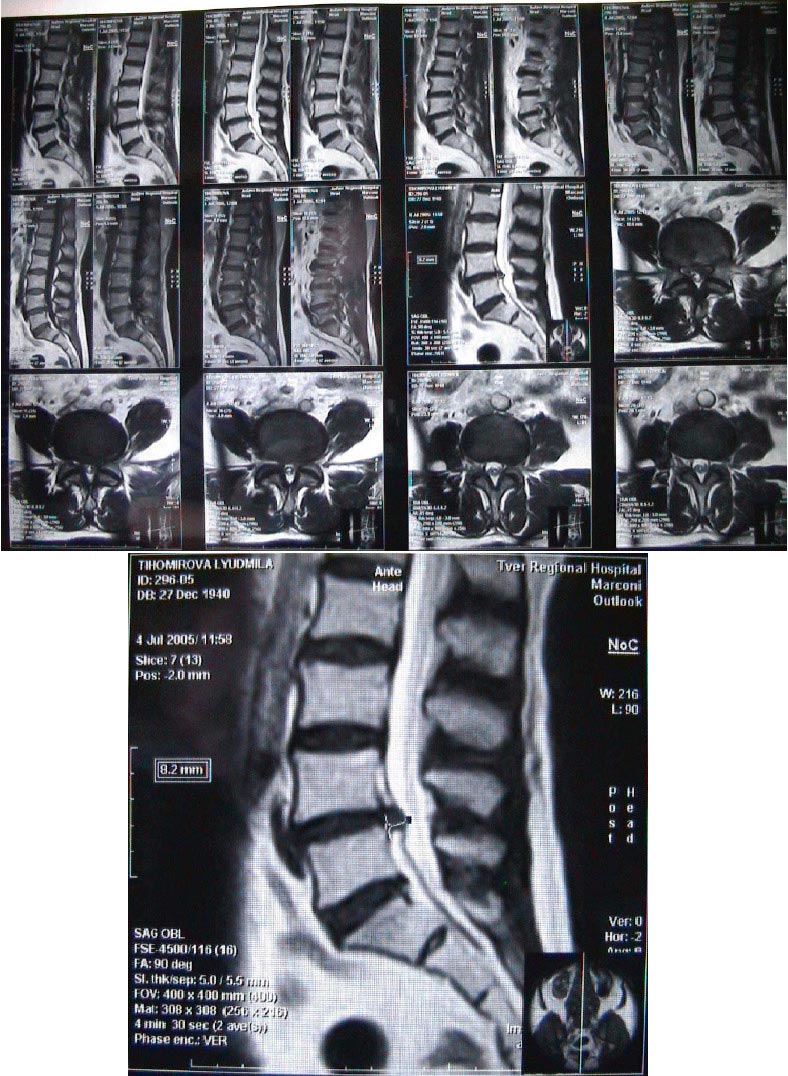

Вопрос:   Уважаемый Василий Геннадьевич, Спасибо за Ваш ответ на мой вопрос номер 335 от 6.7.2005. Как Вы рекомендовали, в приложении направляю Вам снимки моей мамы. Мне хотелось бы знать Ваше мнение и понять, какое лечение необходимо: физиологические процедуры или операция. Мы готовы подъехать, если, по Вашему мнению, есть показания для операции. У мамы болит пояснично-крестцовый отдел позвоночника, больше левая сторона, отдает в левую ногу и ягодицу, нога немеет, менее чувствительные участки: бедро (перед и бок), голеностоп сбоку и снаружи, большие пальцы ноги. Боли начались постепенно примерно два месяца назад, сначала эпизодически после нагрузок, потом усилились, сейчас болит постоянно, при ходьбе болит тазобедренный сустав. Двигательных расстройств и расстройств мочеиспускания нет. 10 лет назад лечилась от остеохандроза пояснично-крестцовой области без боли в ногах с положительным результатом. Другие заболевания есть (и еще какие):щитовидная железа - многоузловой зоб, гипертоническая болезнь сердца второй степени, ИБС, атеросклероз, кисты почек. В Твери сказали, что вероятность остаться инвалидом после операции составляет 95 процентов (!?) Мне бы очень хотелось помочь ей. Буду Вам благодарна. Ирина.

Ответ:   По Вашему описанию имеется компрессия L5 корешка слева, что подтверждается данными МРТ. Имеется достаточно большая грыжа диска L4-5. Учитывая выраженный болевой синдром и объем грыжи, операция формально показана. Однако, учитывая наличие сопутствующей патологии, вопрос этот решается индивидуально. Необходима очная консультация, полноценный неврологический осмотр. Я с сегодняшнего дня в отпуске, завтра уезжаю из Москвы, приеду 28.08.2005, однако Вы можете обратиться непосредственно в отделение (позвоните по тел.252-3556, объясните ситуацию и что снимки можно посмотреть на сайте) или в консультативную поликлинику (ГКБ Боткина, 1-й корпус 3-й этаж, там принимают сотрудники нашего же отделения с 9:00 до 11:00). Для иногородних заведение карточки в поликлинике стоит каких-то денег, но совершенно небольших. С собой надо обязательно иметь снимки и всю возможную мед. документацию (выписки, амбулаторную карту, заключения консультантов в т.ч. исходя из того, что Вы написали - эндокринолога, кардиолога, уролога).